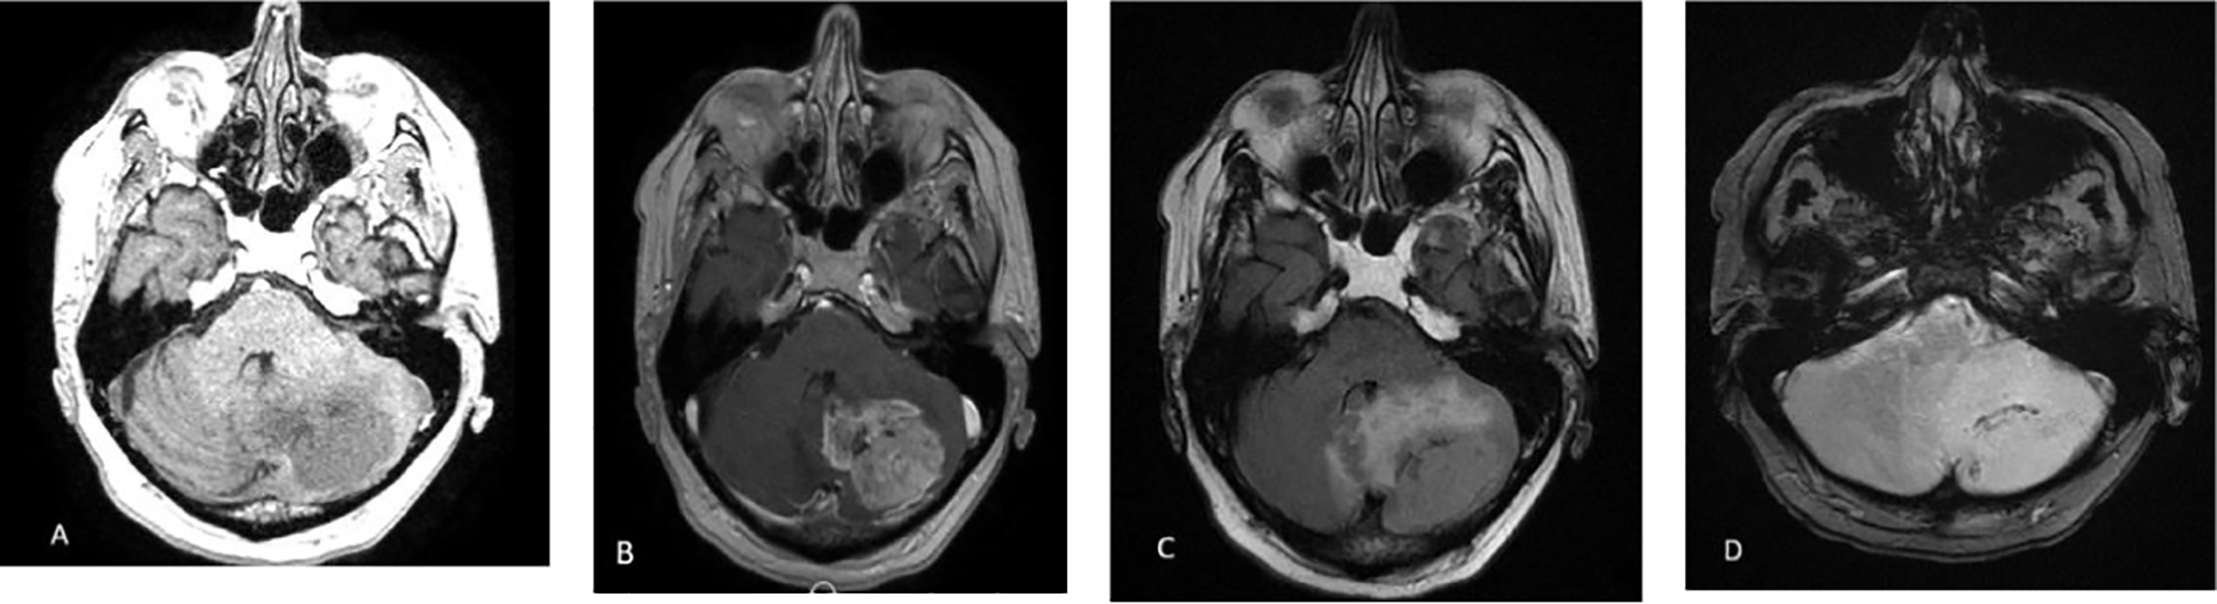

The patient was a 72-year-old man with a history of follicular lymphoma located under the left jaw, treated with surgery followed by radiotherapy. He presented with bilateral post-radiation carotid stenosis that required the placement of several stents. He was also treated with chemotherapy and immunotherapy for a large B-cell lymphoma that developed from a follicular lymphoma of the peritoneal cavity with several associated adenopathies. The patient was considered stabilized during the course, given the excellent metabolic response to the PET scan. The patient presented with balance disorders with dizziness, for which a brain MRI was performed, revealing a large left intra-axial cerebellar tumor exerting a mass effect on the 4th ventricle and the beginning of tonsillar involvement but without overlying hydrocephalus, demonstrating heterogeneous and irregular contrast enhancement (Figs. 1A and 1B) and surrounded by perilesional edema (Figs. 1C and 1D).

Fig. 1. (A) MRI axial T1 revealing a large left intra-axial cerebellar tumor exerting a mass effect on the 4th ventricle. (B) MRI Axial post-contrast T1-weighted image demonstrates heterogeneous and irregular contrast enhancement of the lesion. (C) MRI Axial FLAIR sequences show the tumor surrounded by extensive perilesional edema. (D) MRI Axial T2 sequences show the tumor surrounded by extensive perilesional edema.